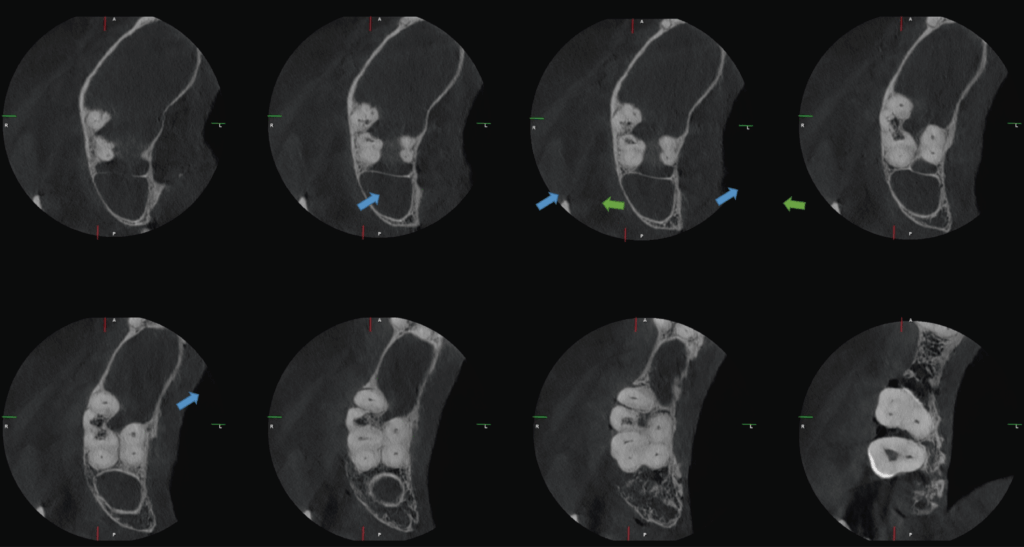

A la evaluación de la tomografía de campo reducido con un tamaño de voxel de 0.75 mm se pudo observar el seno maxilar derecho con presencia de contenido isodenso compatible con sinusitis de origen no odontogénico. Asimismo, se evidencio una reabsorción radicular externa por aposición que compromete la raíz mesiovestibular de la pieza 18 y la raíz distovestibular de la pieza 17 y que se extendía hasta conducto pulpar (visto en cortes tangenciales y axiales) y finalmente se observó hipercementosis de ambas piezas y ausencia del espacio para el ligamento periodontal perirradicular a predominio de zona interproximal de las raíces palatinas compatible con concrescencia.

CORTES AXIALES

CORTES TANGENCIALES